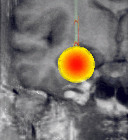

For the laser-induced interstitial thermotherapy, the tumor tissue is coagulated by laser energy as a second step. The propagation of the coagulation process depends on various parameters (e.g., laser energy, absorption, blood perfusion) and has to be controlled whether the coagulation follows the anticipated pattern. Otherwise, the exposition time and dose have to be adapted. Temperature distribution can be controlled by images produced by the interventional MRI system during the intervention.

MR systems can also be used to measure the temperature within the brain during a laser-induced interstitial thermo therapy. As the coagulation process is difficult to predict due to irregularities in tissues and thermo convection, an interventional MR system can be used to control whether the therapy proceeds as planned or whether the plan has to be modified. This asks for a fusion of current MR images with respective images of the therapy planning.